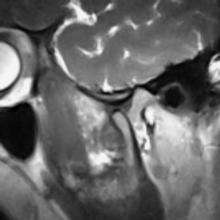

- ↑ Alomar, X; Medrano, J.; Cabratosa, J.; Clavero, J.A.; Lorente, M.; Serra, I.; Monill, J.M.; Salvador, A. (June 2007). "Anatomy of the temporomandibular joint". Seminars in ultrasound, CT, and MR. 28 (3): 170–83. doi:10.1053/j.sult.2007.02.002. PMID 17571700.